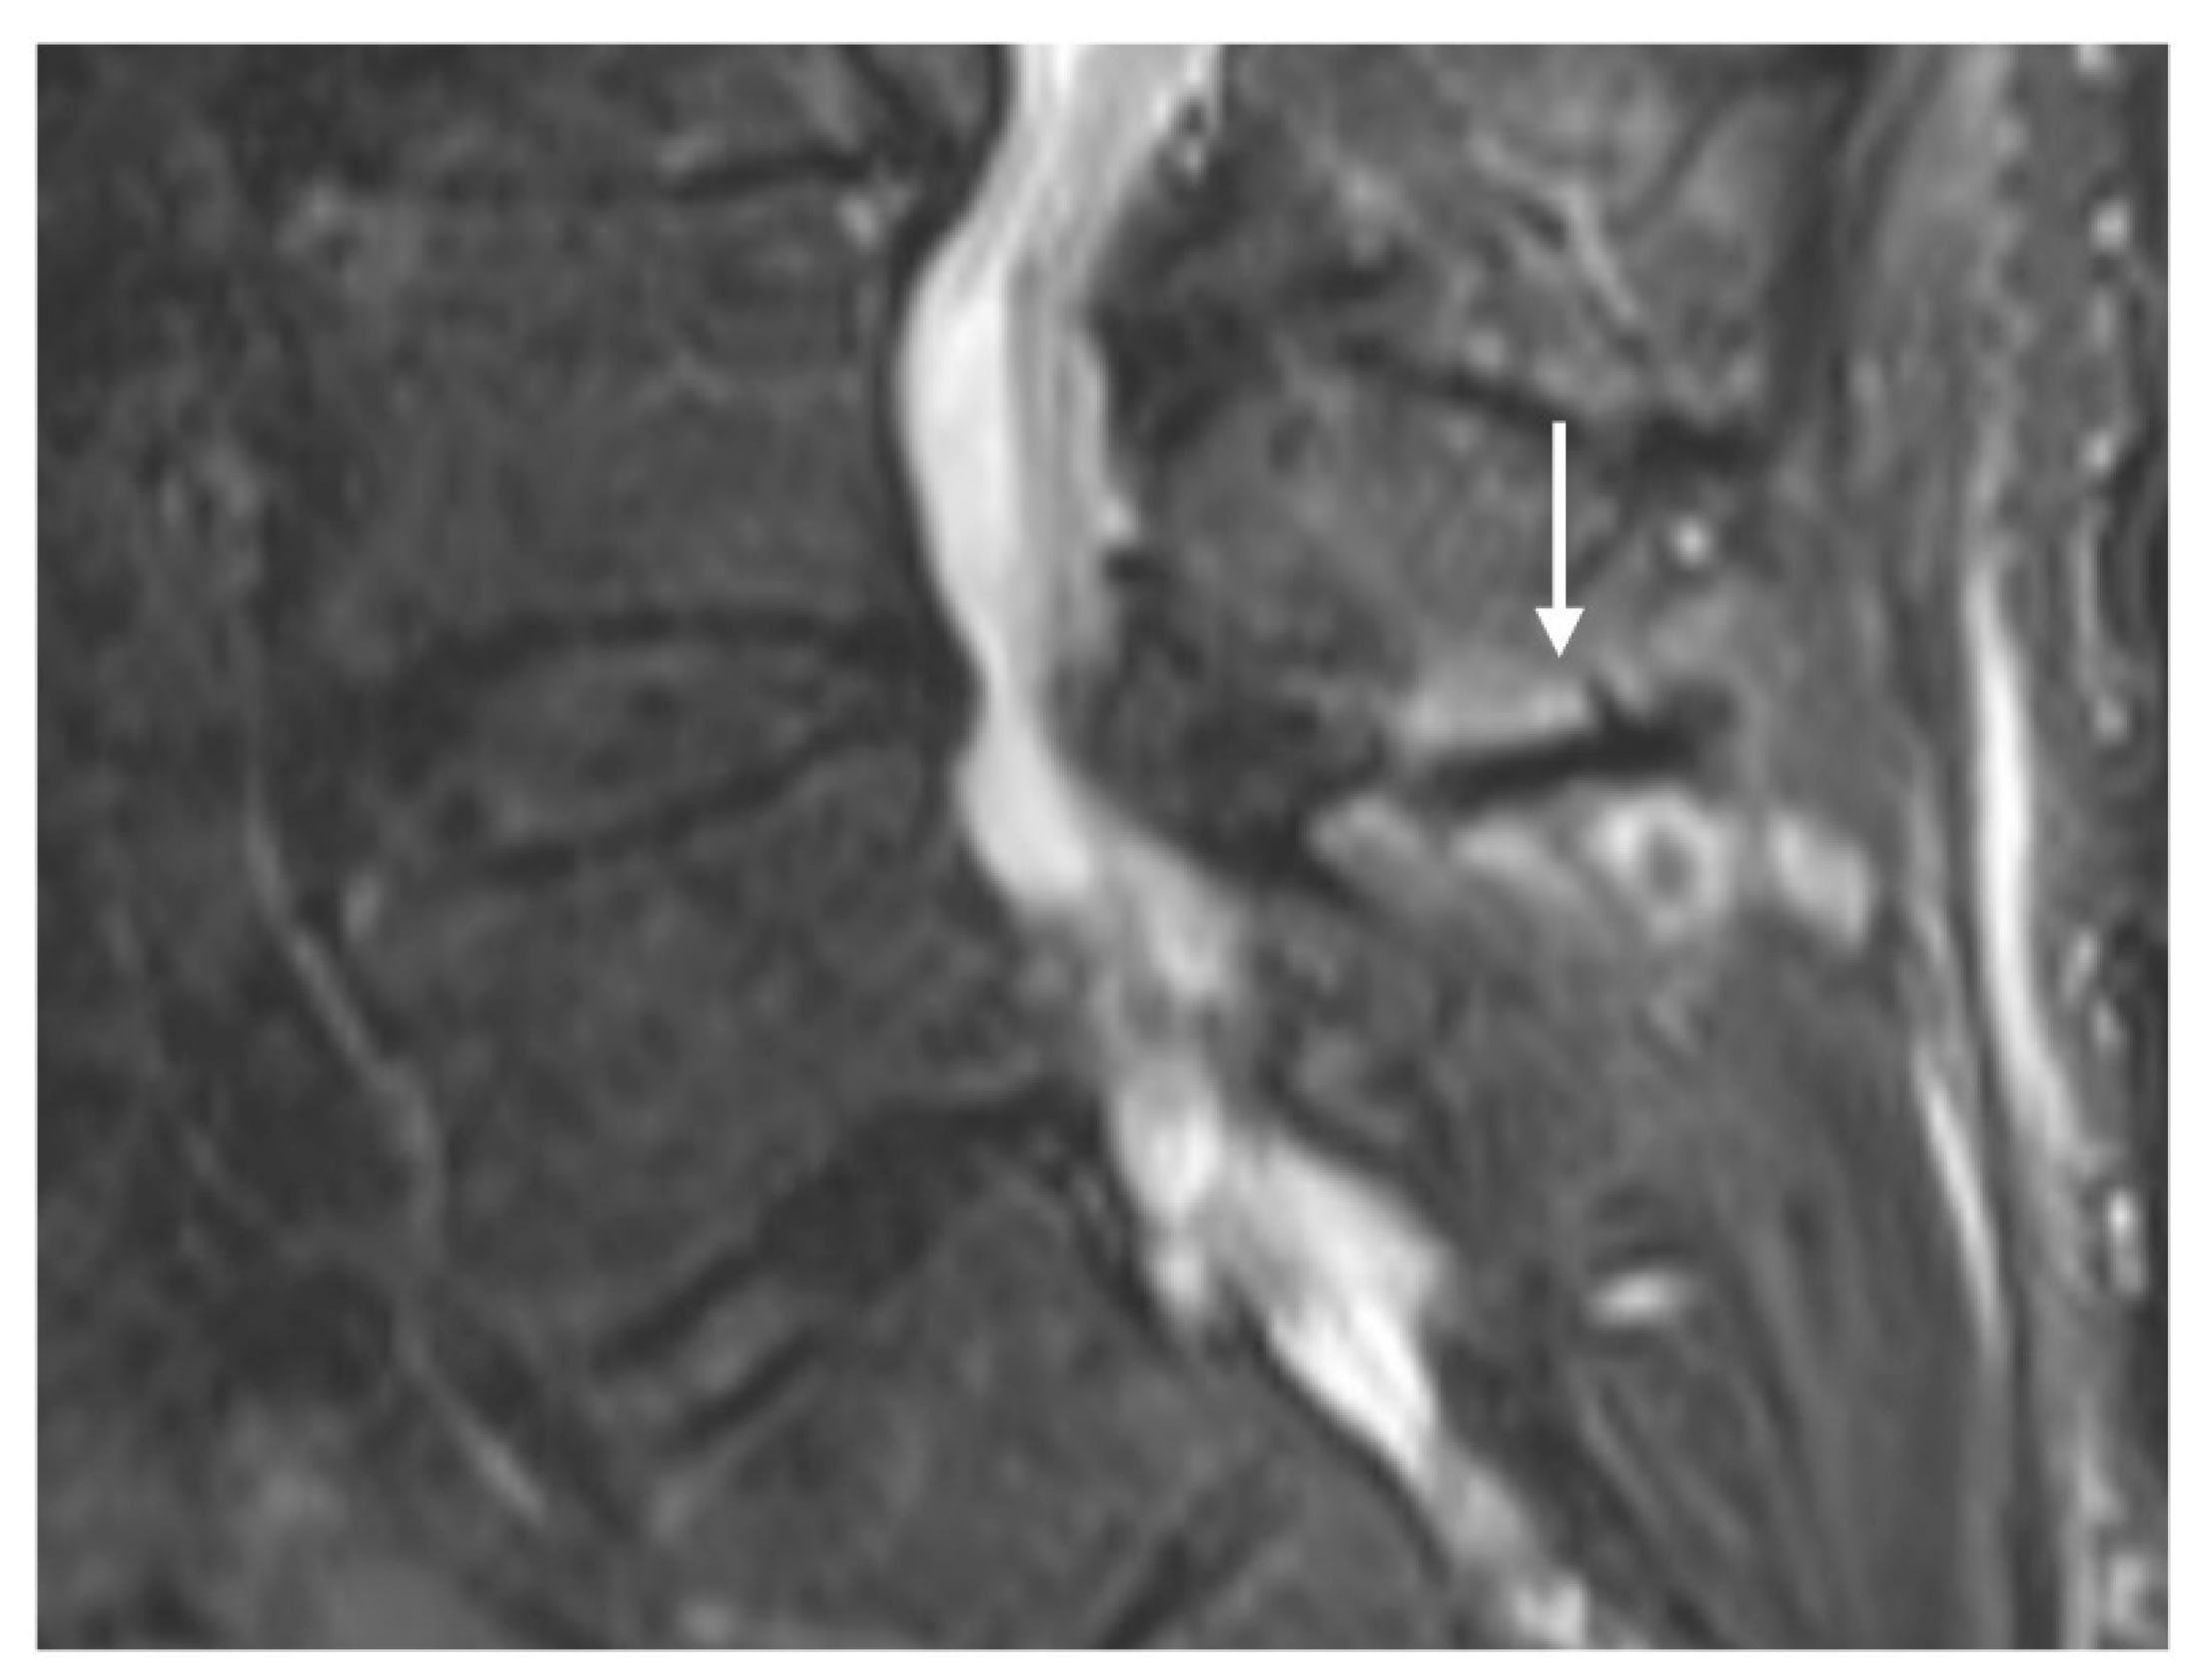

Osteomyelitis of the vertebrae occurs usually due to infection by a single pathogen, with Staphylococcus aureus bacterium being the commonest aetiological organism. The condition occurs primarily due to haematogenous dissemination of infection, but can also occur post-surgery and after trauma. Due to the initial insidious and non-specific clinical presentation, initial diagnosis can be challenging and delayed [42].

While the spine is a common site of infection, endplate involvement is most common, but spinous process osteomyelitis can be occasionally encountered. Correlation with accompanying clinical features and biochemical markers is crucial for accurate diagnosis. MRI is the most sensitive imaging modality, and the earliest abnormality is the presence of subchondral marrow oedema, with reduced T1 signal intensity and increased fluid signal intensity, with enhancement following contrast. This can eventually progress to osseous irregularity and erosion. Inflammatory changes in the adjacent paravertebral soft tissue are also common (Figure 9a,b) [18,42].

Figure 9.

Sagittal (a) and axial (b) STIR sequences demonstrating osteomyelitis of the L4 spinous process, characterised by extensive marrow oedema (white arrow). The oedema also extends to the adjacent laminae in this case, and there is signal change in the adjacent paraspinal muscles, which is a common feature.